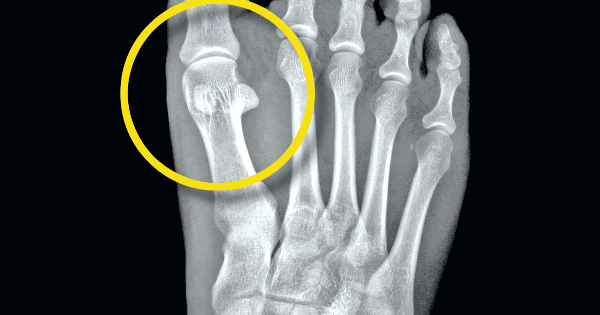

Indications for the inverted orthotic technique. A sharp fracture line is seen separating irregular opposing surfaces of the sesamoid fragments. Treatment options include conservative management with orthotics and immobilization, as well as operative interventions that range from fracture/nonunion fixation to various approaches for sesamoidectomy. Symptomatic sesamoid bone fracture, fracture nonunion, or congenital bipartite sesamoid bone after at least 6 weeks' failure of nonsurgical treatment. Acute fracture of the fibular sesamoid in a young athlete. Indications for the inverted orthotic technique. A chronic sesamoid fracture produces longstanding pain in the ball of the foot beneath the big toe joint. Sesamoid stress injury/fracture stress fractures are relatively common in the sesamoid in athletes or dancers that are required to be on the ball of the it can take many months before the bone heals completely and utilization of an orthotic following the healing would further unload the sesamoid. Sesamoid injuries and sesamoiditis treatment guide. This is combined with the cushioned insole and a. I am a college runner that's been out with a foot injury for almost 8 months now. 94 sesamoid disorders account for 9% of foot and ankle injuries and 1.2% of running 95 injuries.2 although any patient can suffer from various forms of sesamoid disorder. Sesamoid stress fractures may be one of the very worst injuries affecting runners. The two major sesamoid bones in the foot lie under the first metatarsal head. The cast should include the entire hallux to prevent continued metatarsophalangeal dorsiflexion.15 orthotics such as steel shank and rocker sole boots help to reduce stress at the metatarsophalangeal joint.13 stress fractures may take months to. Sesamoid fracture can also cause pain, moderate swelling, and possibly inflammation. An acute sesamoid fracture produces immediate pain and swelling at the site of the.